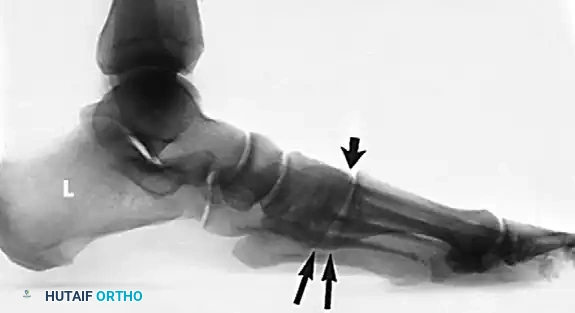

- AP View: Assess the talonavicular coverage angle. Uncovering of the talar head indicates forefoot abduction. The talus-first metatarsal angle (normally 0 degrees) will be elevated.

- Lateral View: Assess the medial longitudinal arch.

- Meary's Angle: The intersection of the longitudinal axis of the talus and the first metatarsal. An angle >4 degrees indicates arch collapse.

- Calcaneal Pitch: Decreased in flatfoot deformity.